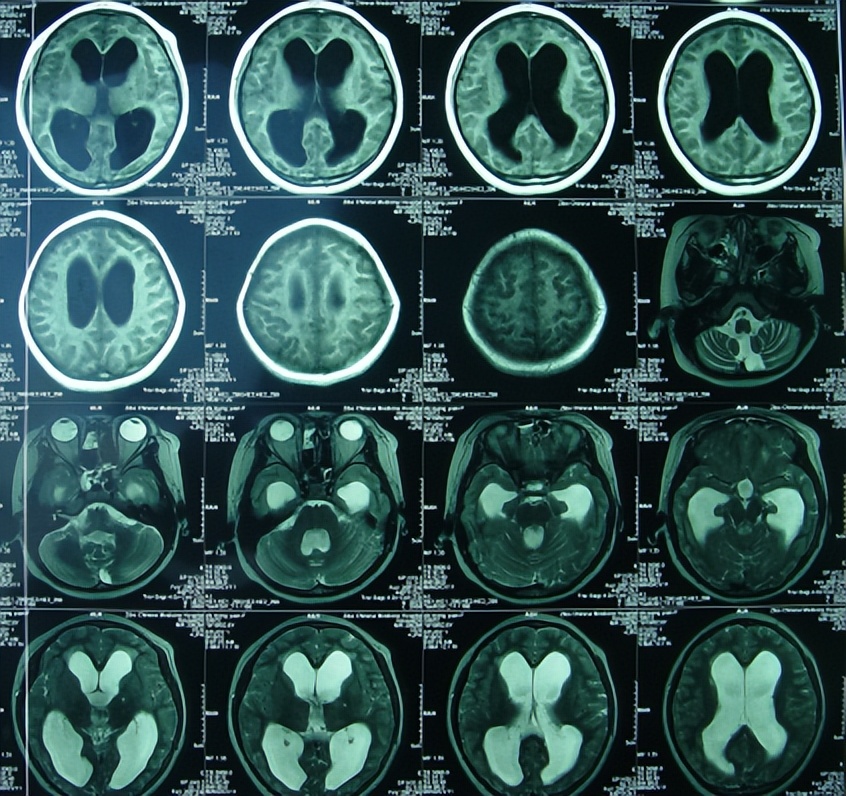

2010年6月9日(治疗17天),突发癫痫大发作,医生下病危通知书。当日复查核磁(图-2)发现脑室有扩张,中度脑积水和脑内多发脑脓肿。

图-2:2010年6月9日头颅核磁

次日即2010年6月10日,请山东省三甲某胸科医院的医生会诊,被诊断为结核性脑膜炎,并同意转入第3家的山东省某胸科医院。